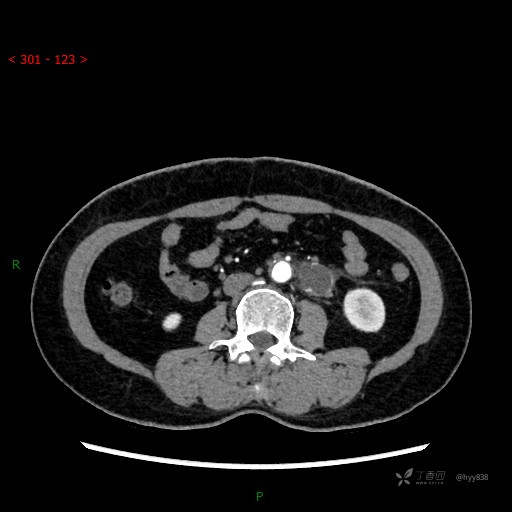

增强动脉期

CT平扫是外院的,因图像质量原因,不方便上传!